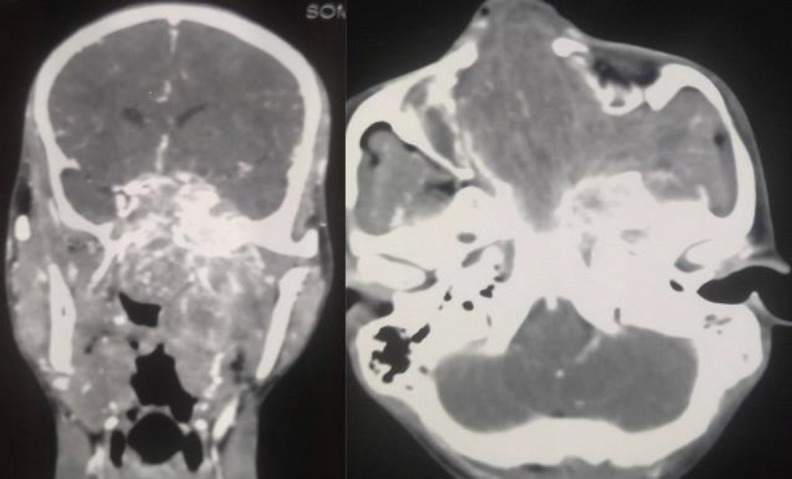

Introduction: In around 10-20% of angiofibroma cases, the tumor penetrates the skull base to involve intracranial structures, posing difficulty in treating them surgically. Today, advancement in skull base surgery has brought about a paradigm shift, and extensive angiofibroma tumors with intracranial extension are approached surgically today with minimal morbidity.

Materials and methods: This study was a retrospective analysis of angiofibroma with significant intracranial extension Radkowski staging IIIb from 2011 to 2021 who came to our center. There were seven children of angiofibroma with significant intracranial extension Radkowski staging IIIb, out of whom, four patients had undergone surgical resection at our center. Three patients underwent surgery by pre-auricular lateral subtemporal approach and one patient by maxillary swing approach. Preoperative embolization was done in all the patients one day before the day of operation.

Results: Gross total removal of the tumor was achieved in all three patients who had undergone pre-auricular lateral subtemporal approach with no permanent complication. All three patients had a minimum follow-up of one year with no recurrence.

Conclusion: The pre-auricular lateral subtemporal approach provides the shortest shallow route to the affected skull base with direct visualization of the tumor base. Hence recommended for angiofibroma with Radkowski staging IIIb.